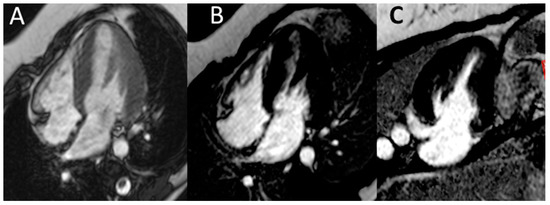

The woman’s medical history was characterized by early onset of non-insulin-dependent diabetes mellitus (at the age of 25), followed by Hashimoto’s thyroiditis at the age of 26. At the age of 30, one year prior to becoming pregnant, during a workup for infertility (ascribed to bilateral fallopian tube obstruction), she was found to have increased creatinine levels and proteinuria. A kidney biopsy was performed, and disclosed focal segmental glomerulosclerosis, with advanced sclerotic lesions (Figure 1). The patient’s mother was affected by Type-2 diabetes and mild CKD but the family history was otherwise uneventful.

The kidney biopsy in this case presents the features of glomerular sclerosis and of glomerulomegalia, thus suggesting a form of focal segmental glomerulosclerosis (FSGS), secondary to nephron loss and to hypertrophy of the remnant nephrons (Figure 1).

Figure 1. Kidney biopsy. Periodic Acid Schiff (PAS) staining, 20X: light microscopy showing three sclerotic glomeruli and a segment of sclerosis in a large hypertrophic glomerulus. Interstitial oedema with mild inflammatory infiltrate is also evident. Arterioles show marked thickening of tunica media.